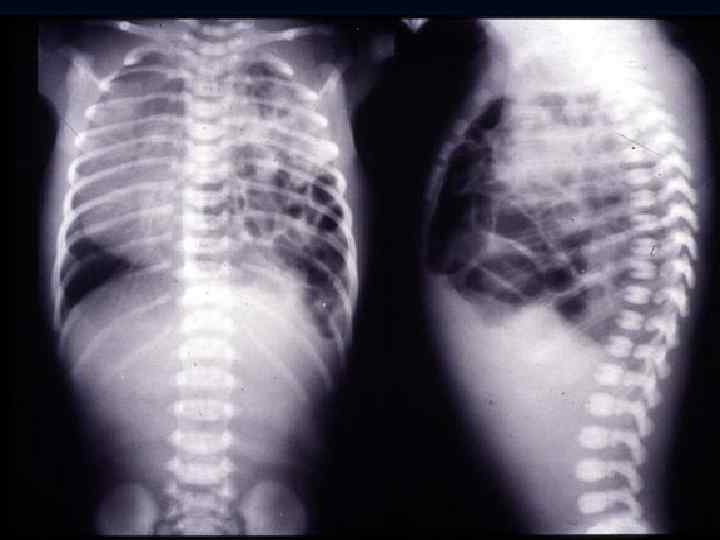

Chest X-ray of the infant 3 days old Reticular granularity of lung fields called "ground-glass” appearance with airbronchogram as the air passages show well against poorly aerated lung.

RDS